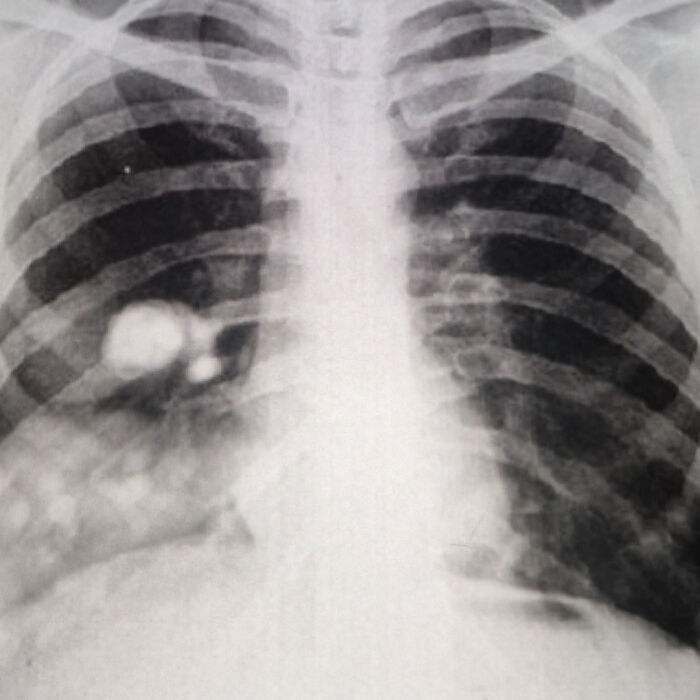

#6 Not What I Expected On A CT Scan Following A Suspected Gallbladder Attack

It’s exactly what it looks like. I’m now terminal at 40 years old. Consider this a PSA: go to the damn doctor when you’re in pain. You never know.

Image source: lickykicky